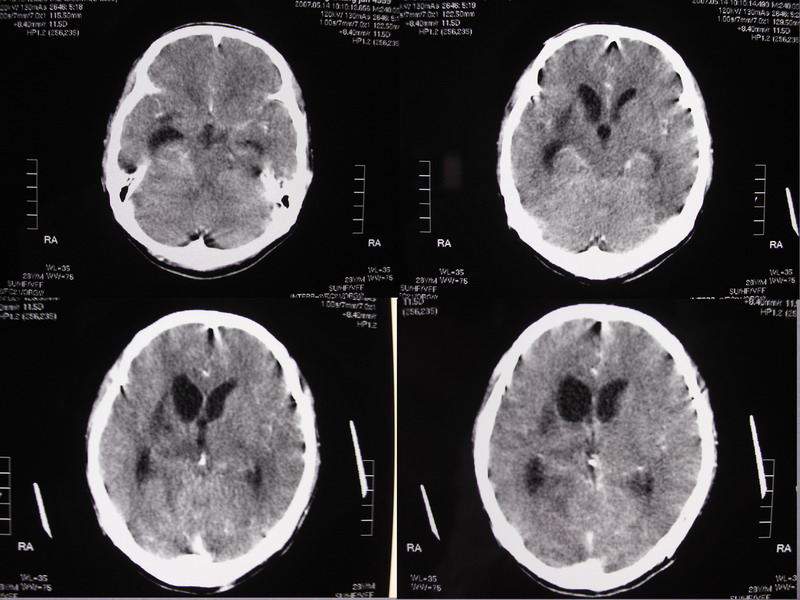

以下是引用余辉在2007-5-14 17:03:00的发言:[br]右侧脑室颞极后方可见高密度块状影,颞极呈杯口状推挤前移,右侧大脑脚及丘脑上部受推挤向对侧移位,右丘脑区结构紊乱,增强扫描病灶有不规则强化,以下部颞极后方为著。胼胝体压部及右枕叶视辐射区低密度改变,右基底节区低密度改变,双侧脑室不对称积水征象,意见:1颞极后方—右丘脑区占位性病变,如室管膜瘤等2脑血管疾病如moyamoya,局部脑血管畸形等3脑膜炎等后遗改变,建议mr及脑血管造影检查[br][br][本贴已被 余辉 于 2007-5-14 17:05:26 修改过]

以下是引用千里草在2007-5-14 15:54:00的发言:[br]考虑:1、双侧梗阻性脑积水;[br] 2、右侧基底节区缺血性脑血管疾病。

以下是引用ssmmxx在2007-5-14 18:05:00的发言:[br]颞极后方—右丘脑区占位性病变,如室管膜瘤等2脑血管疾病如moyamoya,局部脑血管畸形等

以下是引用qiuleiyu在2007-5-14 18:43:00的发言:[br]支持;1,交通性脑积水(病脑后遗征?)2,右基底节及胼骶体压部低密度灶伴轻度占位表现,结合年龄考虑moyamoya,建议dsa.[br]